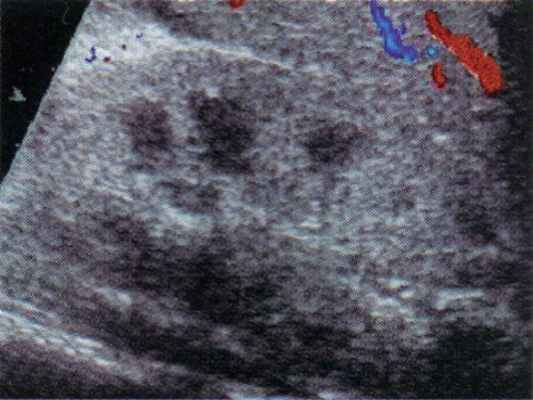

В некоторых случаях при присоединении сердечной недостаточности (перегрузке правых отделов сердца) может определяться необычный характер движения крови в почечной вене, когда в систолу кровь в ней движется из почки, а в диастолу венозная кровь поступает в почку. Это четко прослеживается при дуплексном допплеровском сканировании и допплерографии (рис. 3).

Рис. 3. Необычный паттерн венозного опока из почки (уровень ствола почечной вены) у больного гемолитико-уремическим синдромом.

В диастолу венозная кровь идет в почку (красная стрелка), в систолу основная кровь идет из почки (синяя стрелка).